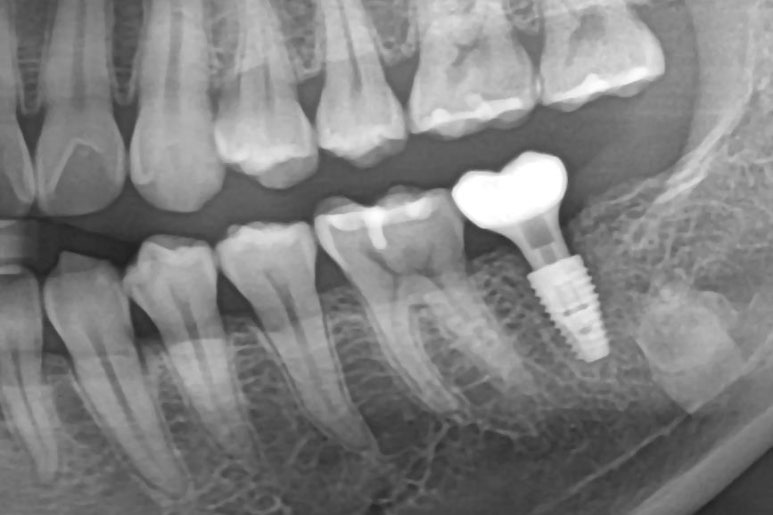

CT 분석 결과

✔ 잔존 뼈 상태 양호

✔ 신경 위치 안전

✔ 초기 고정 확보 가능

👉 그래서

**발치와 동시에 임플란트 식립 (즉시 임플란트)**을 진행했습니다.

✅ 발치 즉시 임플란트 장점

✔ 치료 기간 단축 (2~3개월 이상)

✔ 잇몸뼈 흡수 최소화

✔ 자연스러운 잇몸 형태 유지

✔ 마취 횟수 감소 → 부담 ↓

👉 조건만 맞으면 매우 효율적인 치료 방법입니다.